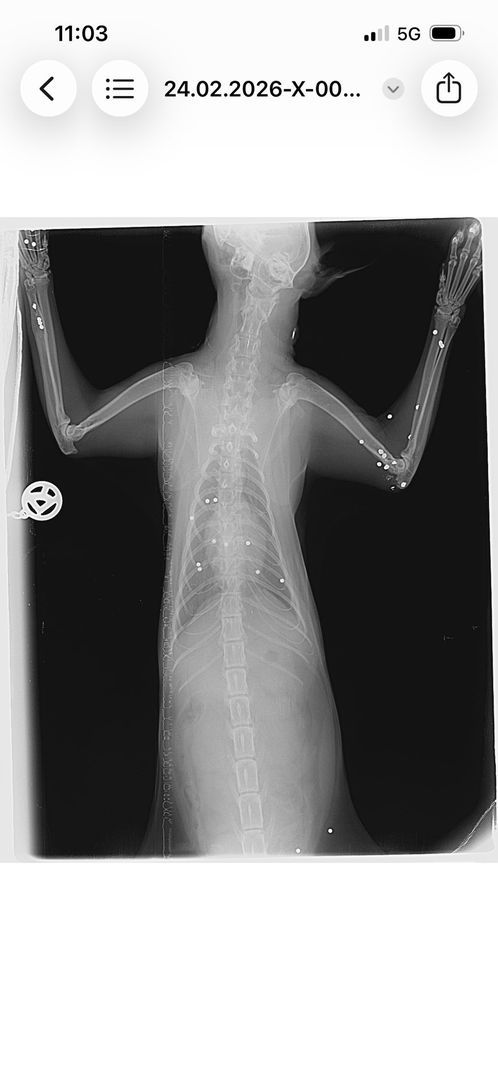

Nach diesem Zwischenfall waren alle vier Katzen verschwunden. Die Betreuerinnen suchten jeden Tag und stellten schließlich eine Kamera auf. Es wurde auch nochmals Kontakt mit dem Jäger aufgenommen – die Ungewissheit war unerträglich, man bat ihn um Ehrlichkeit, in der Hoffnung, Gewissheit zu bekommen und die Suche einstellen zu können. Doch der Jäger stritt weiterhin ab, auf die Katzen geschossen zu haben. Die Suche nach den Katzen ging also weiter, bis schließlich eines Tages eine der verschollenen Katzen auf den Kamera-Aufnahmen zu sehen war, zwei Wochen später tauchte eine zweite Katze auf den Aufnahmen auf. Nach insgesamt sechs Wochen Suche konnten zwei der Katzen endlich gesichert werden. Doch beim Tierarzt der nächste Schock: eine der Katzen war von mehreren Schrotkugeln getroffen worden und musste starke Schmerzen haben.

Nach Auswertung der Röntgenbilder liegt der Schluss nahe, dass die Katze von unten beschossen worden sein muss – die Betreuerinnen erzählen, dass die Katzen immer gerne auf den Balken im Stadl geschlafen haben. Es ist also ziemlich klar, was da passiert sein muss – und es stellt sich die Frage, wie abgebrüht man sein muss, um zu so etwas fähig zu sein. Bei einer Katze wurden die Kugeln, die unmittelbar unter der Haut lagen, mittlerweile entfernt – die tieferliegenden Kugeln sollen erst dann entfernt werden, wenn sie der Katze Probleme bereiten. Man will die Katze im Moment nicht noch mehr stressen. Der Kater, der ebenfalls gesichert werden konnte, ist bis heute so stark traumatisiert, dass eine Untersuchung bisher noch gar nicht durchgeführt werden konnte. Zumindest waren bei ihm aber keine Kugeln unter der Haut zu ertasten. Von den beiden anderen Katzen, die an der besagten Futterstelle versorgt worden waren, fehlt bis heute jede Spur. Es ist leider davon auszugehen, dass sie es nicht geschafft haben.

Hier noch weitere Röntgenbilder der angeschossenen Katze und das Schreiben der Staatsanwaltschaft Augsburg: